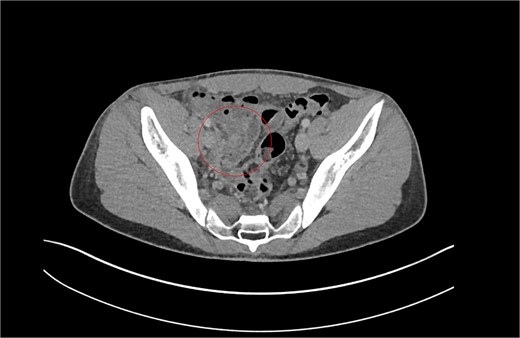

Patient B. Appendiceal stump of Patient B identified within the red circle on CT scan before the second operation.

With a differential diagnosis of stump appendicitis versus nephrolithiasis, a CT KUB was done which revealed no significant findings in the appendix or kidneys—the differential was revised to mesenteric adenitis or inflammatory bowel disease. The patient was counseled to be booked for an outpatient colonoscopy. However, in view of ongoing symptoms, serial examinations and investigations revealed a rising white cell count and CRP to 264. The patient was started on intravenous (IV) antibiotics. A formal CT CAP demonstrated mural thickening and enhancement of the caecal pole and fat stranding (Fig. 2). With a diagnosis of stump appendicitis, IV antibiotics were escalated to metronidazole and piperacillin-tazobactam.

The patient was counseled and consented for a diagnostic laparoscopy and completion appendicectomy. The caecum was mobilized from adhesions to the lateral abdominal wall and the convergence of taenia coli was followed to the appendicular stump. The operation revealed an acutely inflamed long retrocaecal appendiceal stump of ~3 cm length, with pus. Loose suture material was found in the vicinity of the stump. The remainder of the caecum and terminal ileum appeared normal. The patient had an uncomplicated recovery and was discharged 3 days later. Histological examination showed an appendix stump that was 3 cm long with chronic inflammation. There was no obvious malignant activity or periappendicitis.